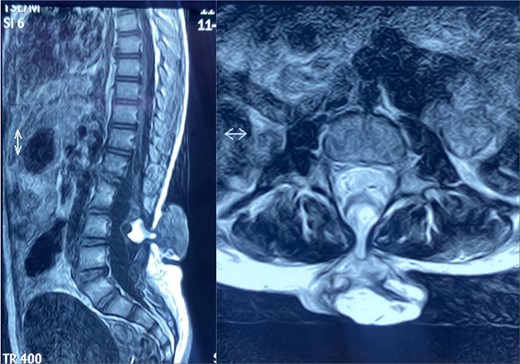

Local examination of the lower back revealed a 5 cm × 4 cm soft, cystic, midline mass located in the lumbosacral region. The mass was tender, with overlying skin showing signs of inflammation, including redness and warmth. There was no discharge or ulceration noted. Magnetic resonance imaging (MRI) of the spine identified a spina bifida defect at the L4-L5 level with a protruding meningocele sac containing CSF but no neural tissue involvement. The findings confirmed the diagnosis of a meningocele complicated by soft tissue infection (Fig. 1).

Sagittal (left) and axial (right) spinal MRI shows a meningocele sac.